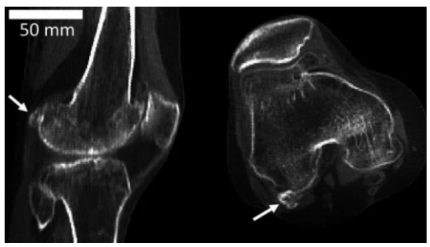

Вчені Імперського коледжу Лондона проаналізували 21 676 випадків, пов'язаних з колінними суглобами за останні 100 років і прийшли до висновку, що у людей поступово з'являється фабела – сезамовидна кістка, яка розташована в сухожиллях з заднього боку коліна, передає ONLINE.UA з посиланням на ВВС.

За словами дослідників, ця кістка була втрачена через еволюцію. Також вдалося з'ясувати, що частота виникнення фабели за цей період збільшилася в три рази.

"Наразі вчені не можуть дати однозначну відповідь про функції цієї кістки, тому що до цього її вивченням ніхто не займався. Можливо, фабела має зменшити тертя в сухожиллях, перенаправивши м'язові сили. Але вона також може викликати біль і заважати при операціях на коліні", - сказано в повідомленні..